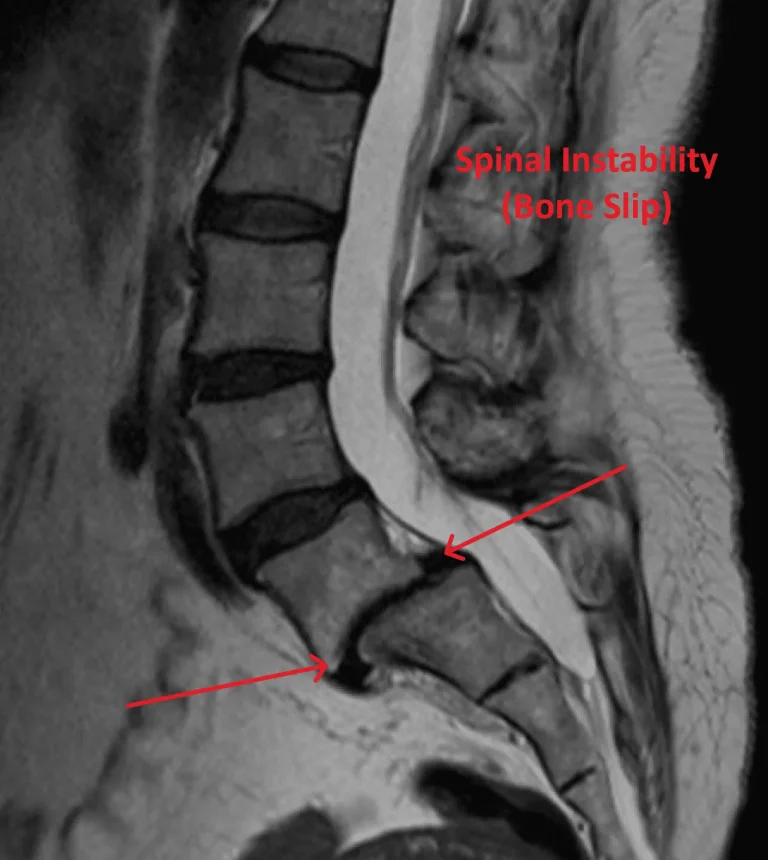

MRI scan showing spinal instability with bone slip, highlighted by arrows and labeled in red text.

Spinal Instability